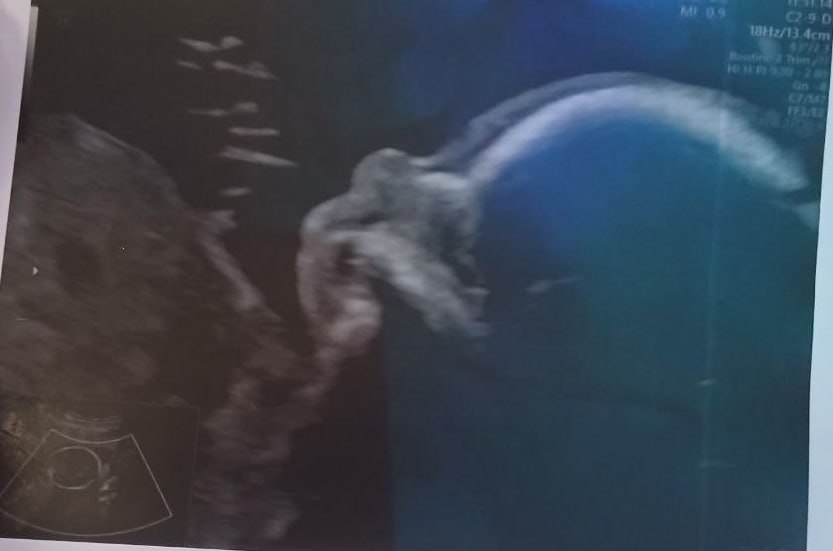

В Питере возбудили уголовное дело после жестокого убийства младенца, которому было всего 16 дней. Предварительно, днем 8 декабря 33-летняя мать, оставшись наедине с ребенком в квартире на улице Ушинского, утопила новорожденного сына.

Женщина объяснила свой поступок отчаянием: у нее пропало грудное молоко, и она пришла к выводу, что не сможет вырастить ребенка. Прокуратура Калининского района взяла на контроль ход расследования.